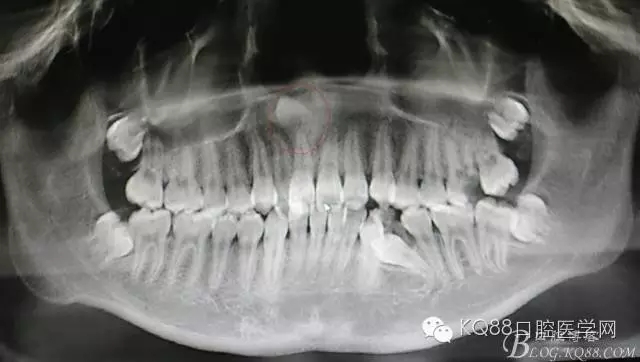

患者、女、13歲,主訴:上前牙擁擠,要求矯正。??茩z查:21腭側(cè)錯(cuò)位萌出,CBCT檢查:11根尖區(qū)有一倒置多生牙,多生牙會(huì)影響正畸治療,建議外科手術(shù)拔除多生牙。患者同意治療方案、簽知情同意書。

圖1.CBCT全景片重建檢查:11根尖區(qū)上方有一倒置多生牙